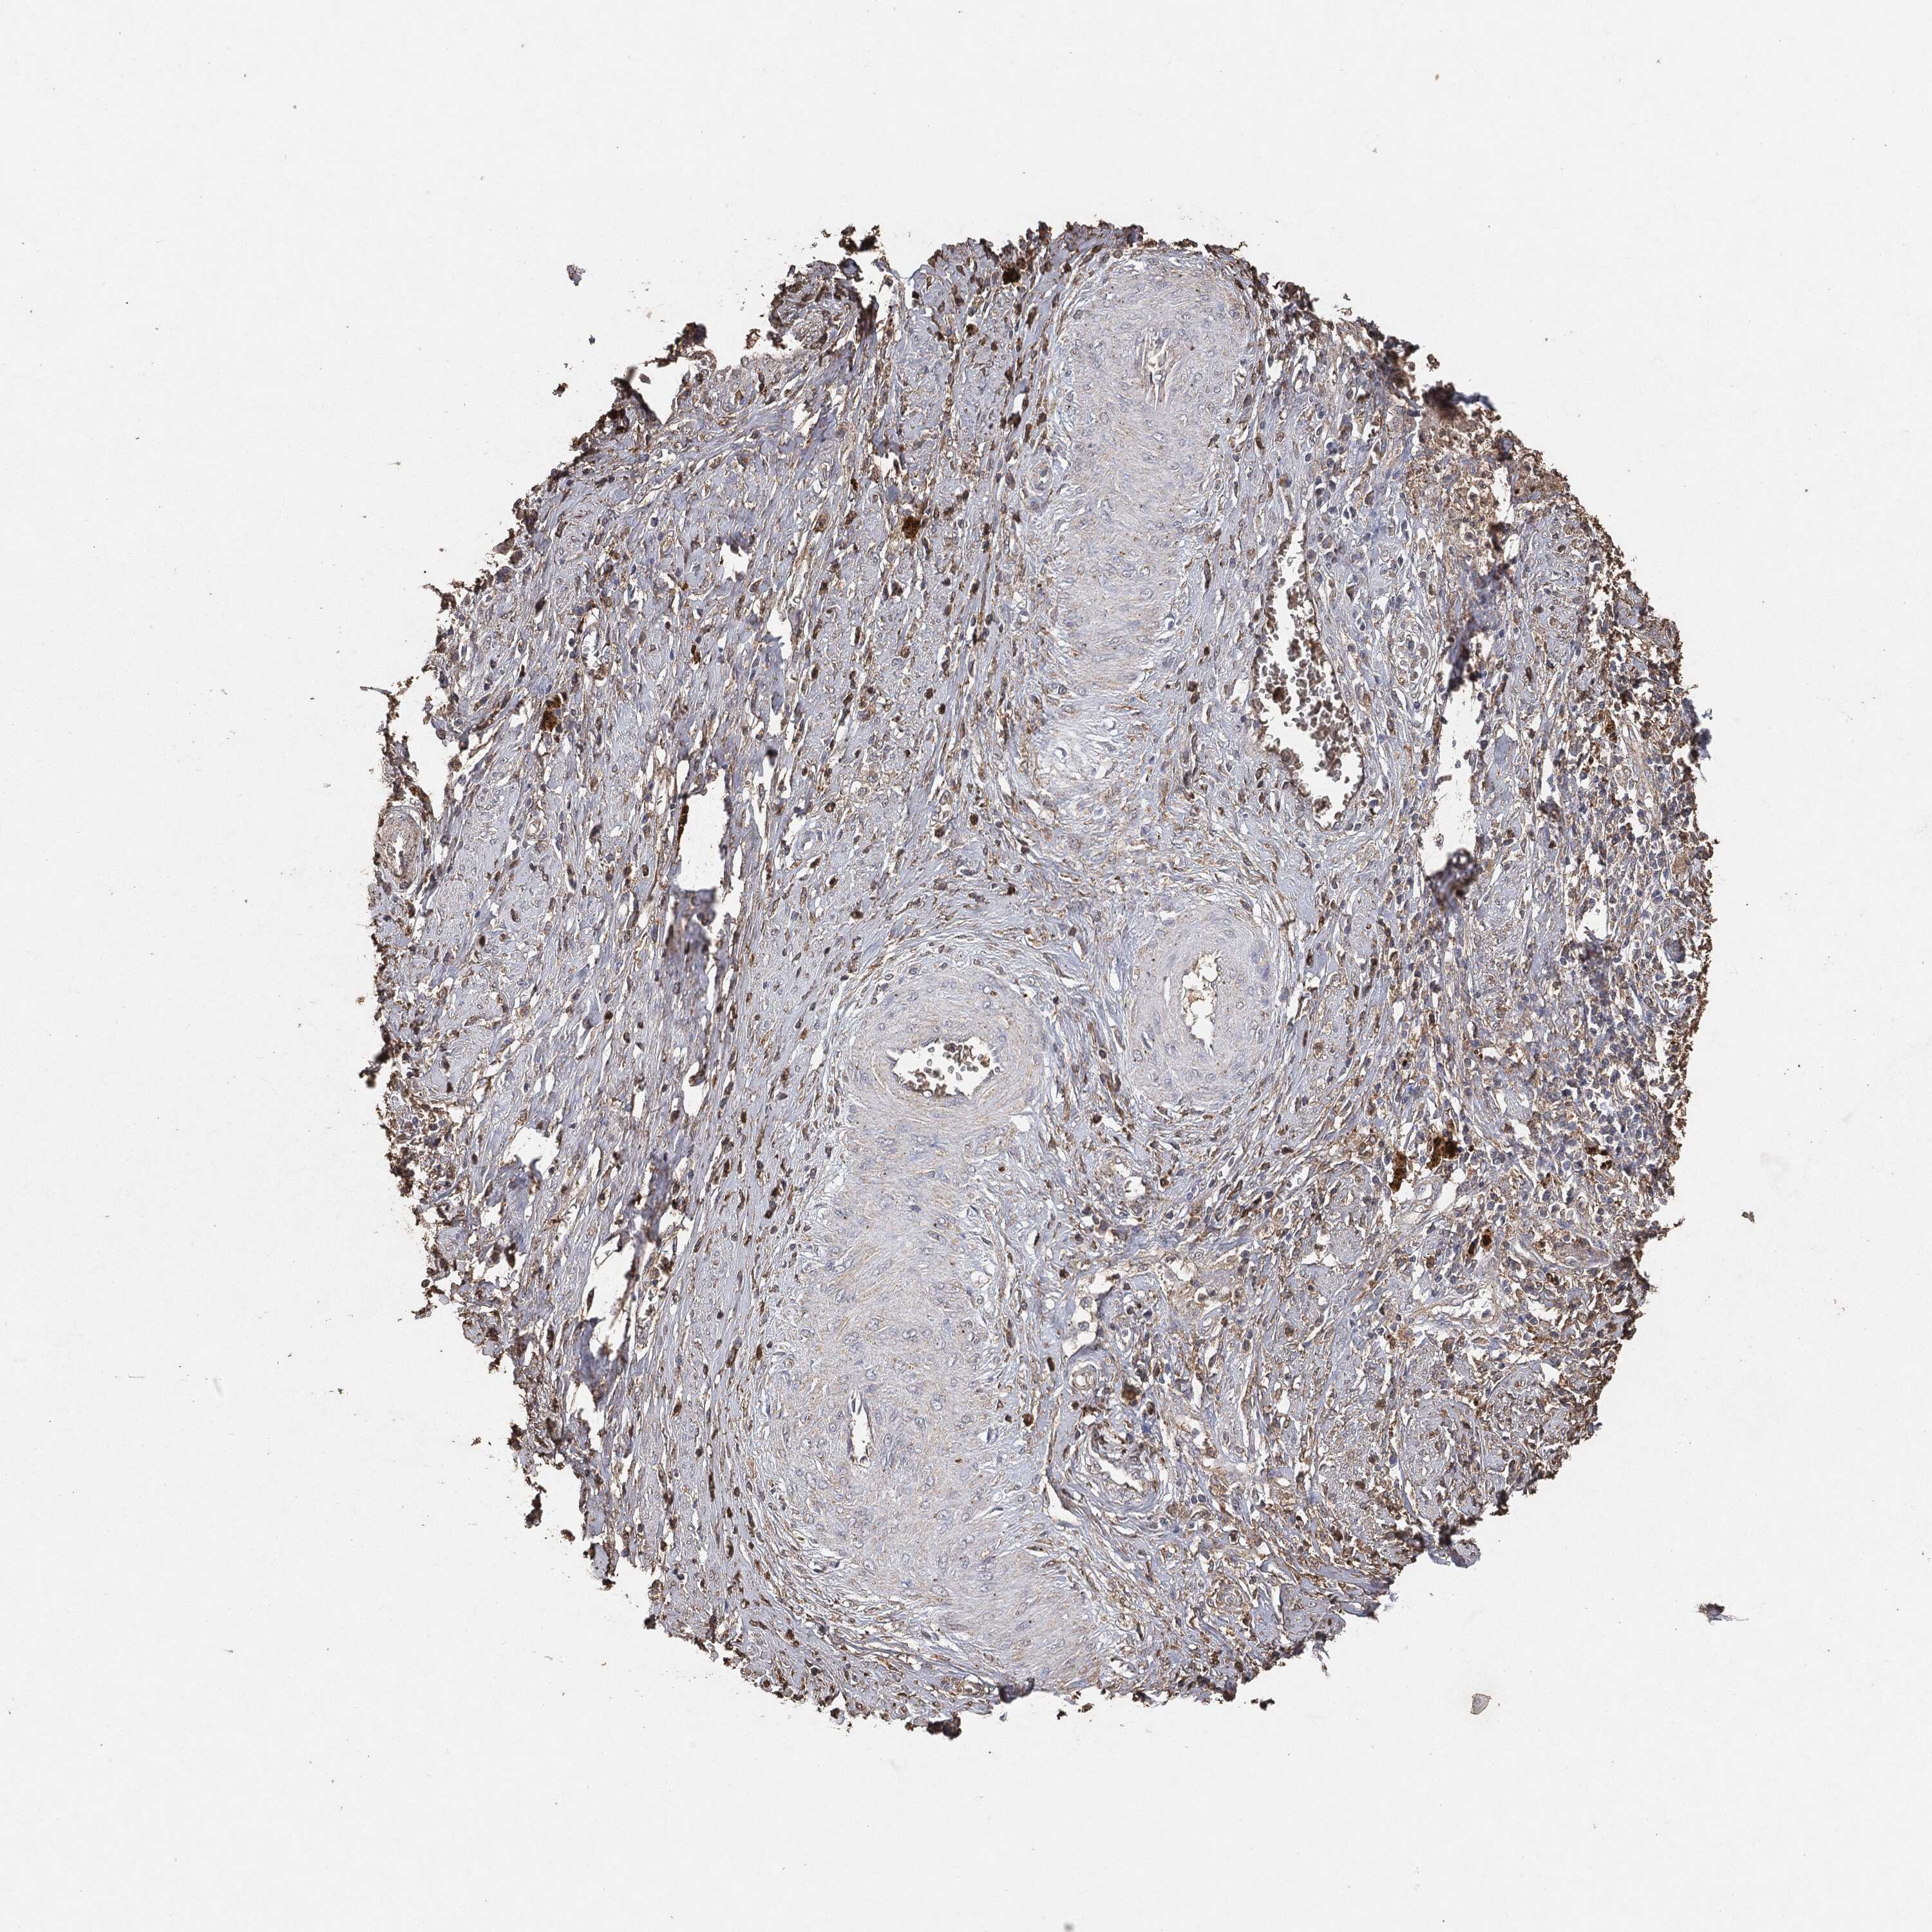

CERVICAL CANCER - Protein expressioni

A mouse-over function shows sample information and annotation data. Click on an image to view it in a full screen mode. Samples can be filtered based on level of antibody staining by selecting one or several of the following categories: high, medium, low and not detected. The assay and annotation is described here.

Note that samples used for immunohistochemistry by the Human Protein Atlas do not correspond to samples in the TCGA dataset.

Antibody stainingi

Antibody staining in the annotated cell types in the current human tissue is reported as not detected, low, medium, or high, based on conventional immunohistochemistry profiling in selected tissues. This score is based on the combination of the staining intensity and fraction of stained cells.

Each image is clickable and will lead to virtual microscopy that enables deeper exploration of all samples and also displays staining intensity scores, fraction scores and subcellular localization as well as patient and tissue information for each sample.

Squamous cell carcinoma, NOS